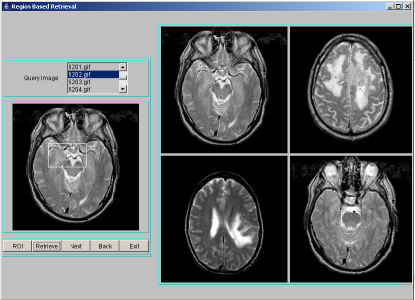

A data structure based on hashing technique is used to store all images along with the texture feature data. A combined index is adopted to point to all similar images in terms of the texture features. When a query is made based on an example image, the example image is processed for index value. Only those images that are in the same hash bucket as those of the queried image are compared for similarity. For each image in the database, segmentation procedure discussed in section 2 is applied to identify region-of-interest and describe segmented region by texture features: entropy, energy and contrast. The texture features extracted are quantized to integer values between 0 to 9. The combined index of these features is: , where [ ] represents quantization. Each combined index stores feature data along with the image object. For a query image, after finding the region-of-interest, the above mentioned texture features have to be computed, quantized and the combined index derived. Only those images that are stored at the combined index matching those of the query index, are extracted as resultant target images for a given query image. These resultant images are sorted using Euclidean distance measure in the decreasing order of similarity against the query image and displayed four images at a time using JAVA-AWT based GUI. A few representative snapshots of region-based indexing and retrieval are shown in Figure 1. Hash table offers very fast insertion and searching. Irrespective of the size of the data, insertion and searching can take close to constant time . Not only are they fast, hash tables are simple and easy to implement. Searching using hash tables are significantly faster than using tree, which operate in time.

|

|